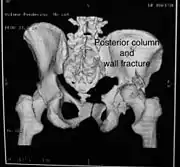

Posterior columnAs with posterior wall injury, this also typically occurs due to dash board injury. Posterior column + Posterior wallThese fractures are extensions of elementary fractures. With the involvement of the posterior wall, the difficulty in treatment increases. These fractures are rarely amenable to non-surgical treatment. Due to posterior wall fracture, the hip is usually dislocated posteriorly, requiring immediate reduction of dislocation and surgical reconstruction after a few days.

The posterior column with posterior wall fracture occurs due to dashboard injury. The anteroposterior view may give clues to these injuries. Judet views and CT scans help in knowing the extent of the injury.